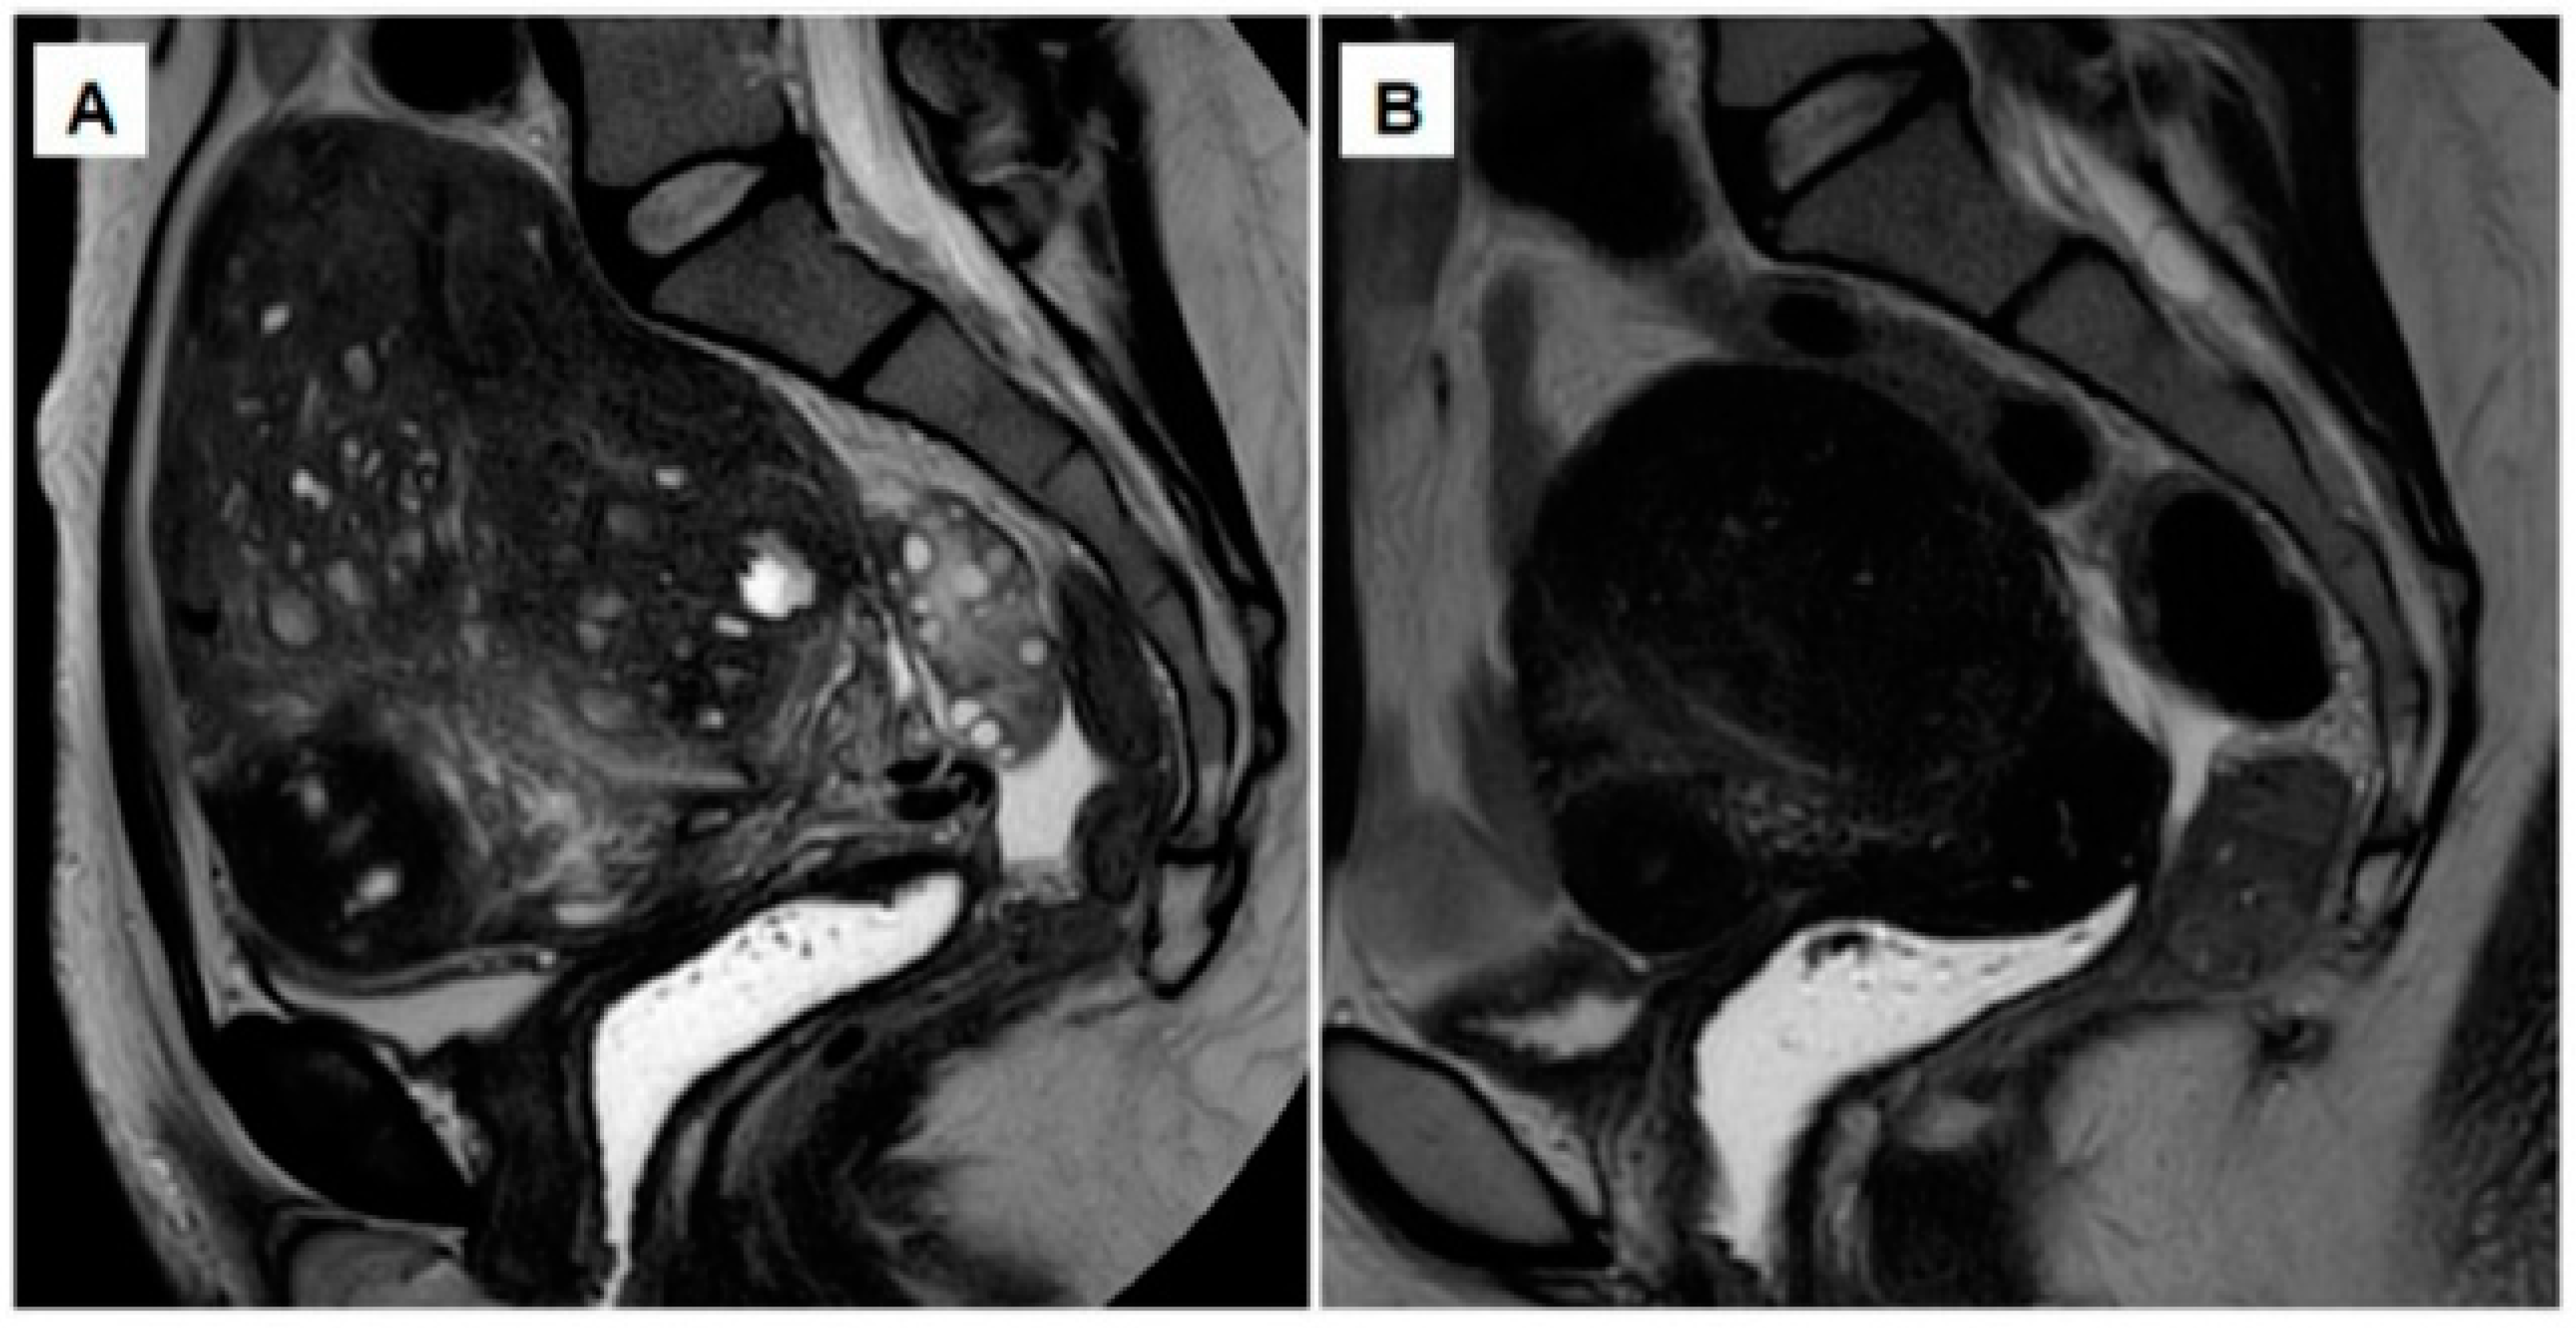

- Imaoka, I.; Ascher, S.M.; Sugimura, K.; Takahashi, K.; Li, H.; Cuomo, F.; Simon, J.; Arnold, L.L. MR imaging of diffuse adenomyosis changes after GnRH analog therapy. J. Magn. Reason. Imaging 2002, 15, 285–290. [Google Scholar] [CrossRef]

- Andersson, J.K.; Pozzi Mucelli, R.; Epstein, E.; Stewart, E.A.; Gemzell-Danielsson, K. Vaginal bromocriptine for treatment of adenomyosis. Impact on magnetic resonance imaging and transvaginal ultrasound. Eur. J. Obstet. Gynecol. Reprod. Biol. 2020, 254, 38–43. [Google Scholar] [CrossRef] [PubMed]